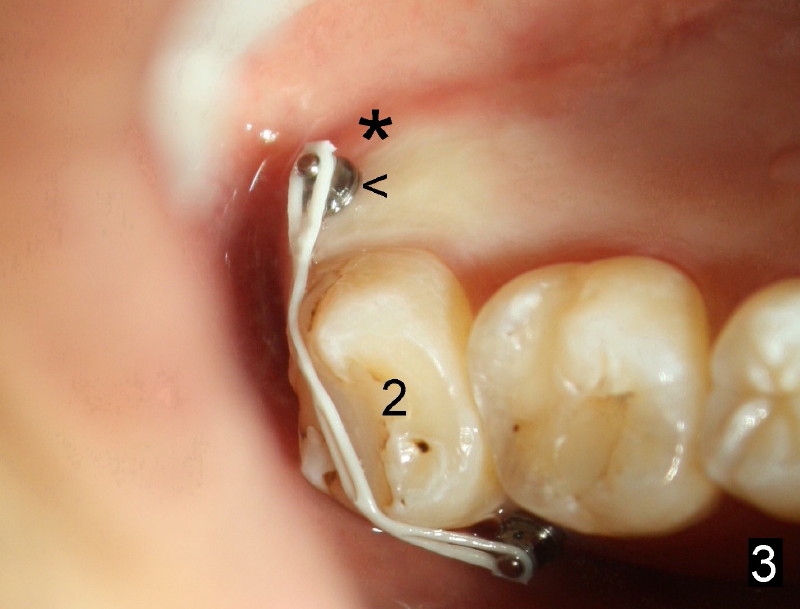

Eight mm of Ancor mini-implant is placed on the mesiobuccal of #2, whereas 6 mm on distopalatal (Fig.3,6 <) without sign of hemorrhage. But a few days later, the patient's father calls, saying that one of mini is out (palatal). The palatal mucoperiosteum is thicker than buccal. Longer mini-implant should have been used (8 or 10 mm). The excuse for short mini in the palate is that there is not much soft tissue (presumably hard tissue) distal to #2. In fact, the patient is dental phobic. Who will faint first dealing with the fearful patient for the same procedure for a second time?

Fortunately, the kid is getting more mature each time. He is pleased to hear that no needle is needed. Another mini company (Tomas, Dentaurums) recommends topical and no incision for mini. Without local anesthesia, the patient may feel pain if a long mini is touching root surface. To get decent anesthesia, Cetacaine (a topical usually used for laser) is applied to the mucosa for prolonged period of time. A 10 mm Ancor mini is loaded in a 16:1 reduction slow-speed handpiece driven by air turbine. The mini penetrates the mucosa without incision or pilot drill. Judged by healed wound, the new mini is placed more mesioapical than the earlier one (Fig.3 *) in hope to catch bone. It appears that the whole hard palate has attached gingiva. The portion near the teeth has thicker gingiva. Mini should be placed in thick gingiva to reduce tissue reaction.

Mini penetration does create soft tissue shaving, which may cause epithelial entrapment and therefore potential mini loosening. At time of placement, it is a minor issue, in comparison to violation of root surface. As the mini goes down, torque builds up. Finally the handpiece halts. Then use a wrench to slowly rotate the mini down while watching for patient's reaction. It appears that the mini eventually has resistance (touching root surface?). The mini does not seat completely (Fig.4 >, as compared to Fig.3 <), but it is solid. When power chain is loaded, it is apparent that the patient feels more pressure upon #2. The patient tolerates the procedure with topical well. It feels like that champagne is needed for celebration. Sweeter is taking and looking at immediately post-op PA (Fig.7 >).